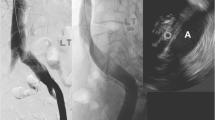

OCT images of untreated normal vessel segments revealed a characteristic three-layered appearance. While OCT clearly distinguished tunica media and tunica adventitia layers as defined by histology, it was more difficult to discern tunica intima, inner elastic membrane, and transition between tunica media and tunica adventitia. The external elastic membrane was not visualized by OCT (Fig. 1). Tables 1 and 2 summarize qualitative OCT image criteria of the normal venous wall and agreement between the consensus of OCT image criteria and the consensus of histologic diagnosis.

a–d Histological (hematoxilin/eosin staining; magnification 40×) and OCT images of a normal venous segment. a Histology shows a three-layered appearance of the vessel wall with clear differentiation of the tunica intima (I), tunica media (M) and tunica adventitia. The vertical lines represent fixation artifacts (asterisks). b In the corresponding OCT image there is a signal-rich appearance of the tunica intima (I), while the tunica media (M) is predominantly low in signal, but traversed by several high-signal collagenous and elastic fibers. The tunica adventitia (A) appears high in signal. c, d Zoomed-in views of a and b for better delineation of I, M and A (white lines indicating transition between I/M and M/A, respectively). C artifact caused by the OCT catheter, L lumen. Bar=1 mm

a–c Subcutaneous bovine leg vein before and after RFA. a OCT image before RFA treatment reveals normal three-layered appearance of the vessel wall with normal lumen width. b OCT image immediately after RFA treatment shows homogenization of signal intensity with loss of the normal wall structure and significant lumen loss. c Histological cross section (hematoxilin/eosin staining; magnification 40×) with a circular swelling of the entire vascular wall, reduced clarity of vascular contours and significant increase in the thickness of the vascular wall. C artifact caused by the OCT catheter, L lumen. Bar=1 mm

a–c Subcutaneous bovine leg vein before and after ELT with high energy density (35 J/cm). a OCT image before ELT reveals normal three-layered appearance of the vessel wall with normal lumen width. b OCT image immediately after ELT treatment demonstrates a severe thermal lesion with carbonization and transmural vessel wall disruption with preserved vein structure of the contralateral wall segment. c Histological cross section (hematoxilin/eosin staining; magnification 40×) with transmural destruction of the vascular wall and surrounding perivascular tissue. C artifact caused by the OCT catheter, L lumen. Bar=1 mm